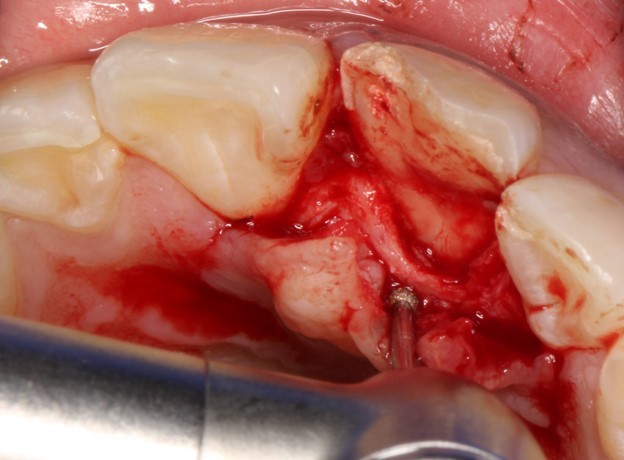

Лечение: Под местной анестезией убрали часть сколотого зуба

Отслоили мягкие ткани (а)

Редуцировали часть костной пластинки (б)